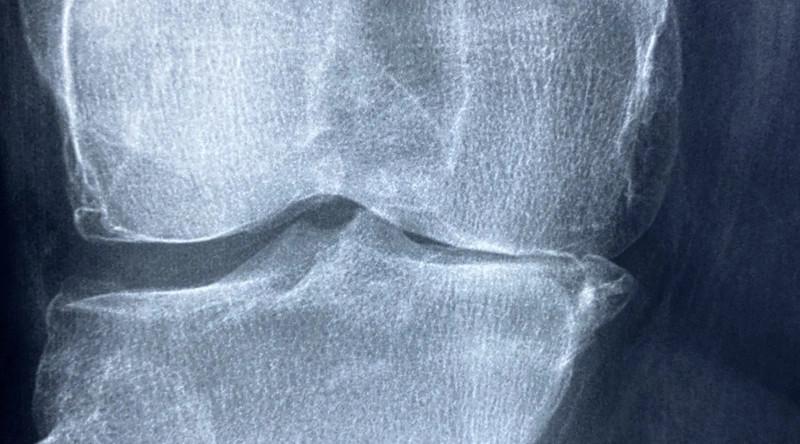

무릎 십자인대 파열이 의심될 경우, 반드시 병원을 방문하여 검사를 받아보아야 합니다. 의사는 환자의 증상을 바탕으로 이학적 검사를 시행하고, 엑스레이 또는 MRI 촬영을 통해 손상의 정도와 정도를 확인합니다. 이러한 검사를 통해 무릎 관절의 다양한 구조물에 대한 손상 여부를 판단할 수 있으며, 적절한 치료 방법을 결정하는 데 중요한 기초 자료가 됩니다.

검사 결과에 따라 비수술적인 방법과 수술적인 방법이 결정될 수 있으며, 이는 환자의 현재 상태와 스포츠 활동 수준에 따라 다양하게 달라질 수 있습니다. 빠르고 정확한 진단은 성공적인 회복을 위한 첫걸음입니다.